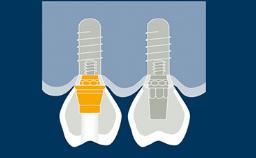

When providing a patient with an implant-supported rehabilitation, clinicians must decide whether to fabricate a provisional prosthesis or go directly to the definitive prosthesis.

Several factors play a role in making the correct decision. These involve the location of the implant anterior or posterior site, the number of implants, the need to shape tissue, as is often seen with adjacent implants in the anterior area, and the need for occlusal support.

The patient’s wishes may also play a role in this decision. This module will highlight the indications, materials and techniques for fabrication and utilization of an implant-supported provisional prosthesis.